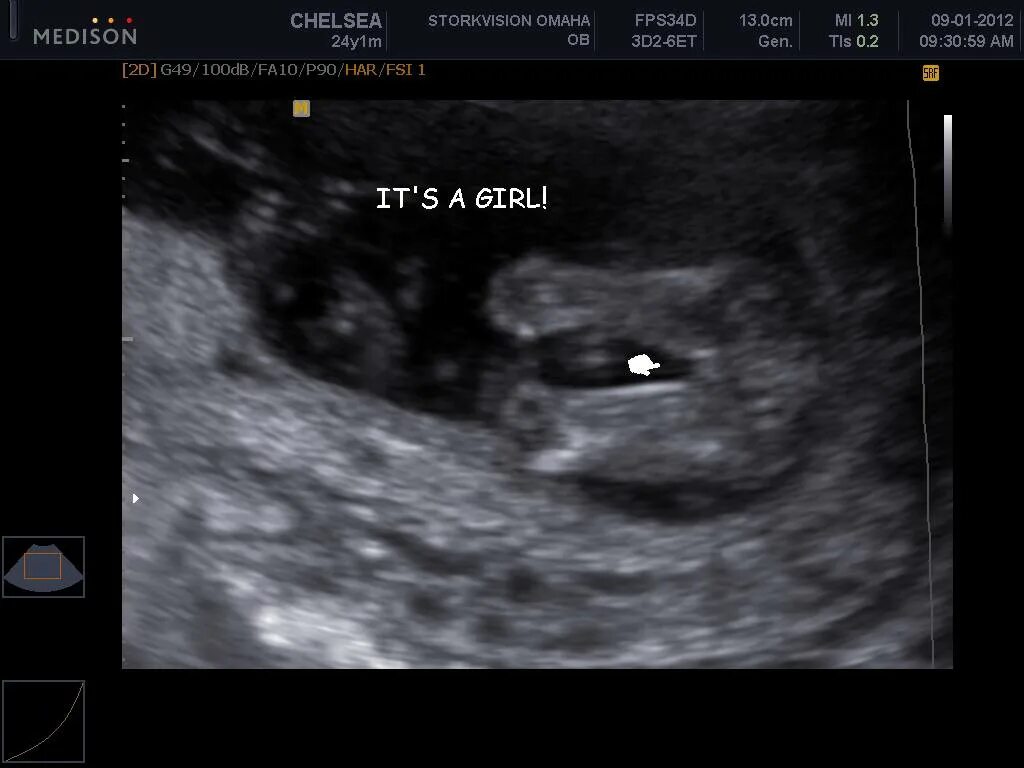

Как определить пол ребенка в 12 недель